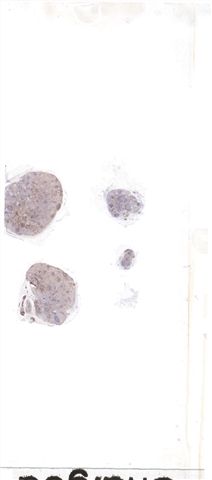

| 大体所见: | 颈部淋巴结4枚,直径0.2cm,0.4cm,0.8cm和1cm。 |